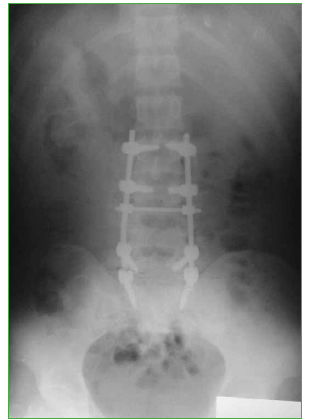

Se decide efectuar una cirugía con abordaje posterior lumbosacro, descompresión posterolateral directa por técnica de tipo eggshell, con resección del arco posterior de L4 y reducción de los fragmentos en retropulsión.25-27 Se realiza artrodesis lumbosacra larga L2-S1 (Figuras 4 y 5).

Figura 4.

Caso 1. Control radiográfico posoperatorio (perfil).

Figura 5.

Caso 1. Control radiográfico posoperatorio (frente).

El paciente evoluciona favorablemente con cicatrización de la herida quirúrgica. Comienza con rehabilitación en el posoperatorio inmediato. Se corrige la cifosis segmentaria con medición radiográfica a los seis meses de la cirugía adecuada (Cobb L3-L5 33°, lordosis lumbar 44°, incidencia pelviana 44°, IP-LL 0°, inclinación de la pelvis 18°). El paciente recupera la sensibilidad por completo y evoluciona con una secuela deficitaria parcial motora de raíz L4 izquierda, extensión activa del pie grado 3 (vence gravedad). La TC de control a los dos años muestra la consolidación (Figura 6). Vuelve a montar a caballo (Figura 7 y video).